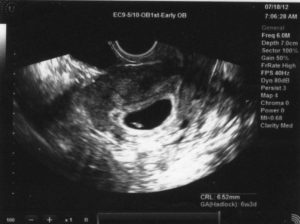

Чтобы исключить такое состояние, даже после получения положительного результата теста на беременности, стоит записаться на ультразвуковое исследование. Обычно оно проводится вагинально при помощи специального датчика.

Но так как многие женщины бояться, что такое обследование вызовет выкидыш, можно записаться на УЗИ на полный мочевой пузырь.

В таком случае врач-узист сделает процедуру абдоминально, что означает проведение процедуры на поверхности живота при помощи небольшого датчика и специального геля.